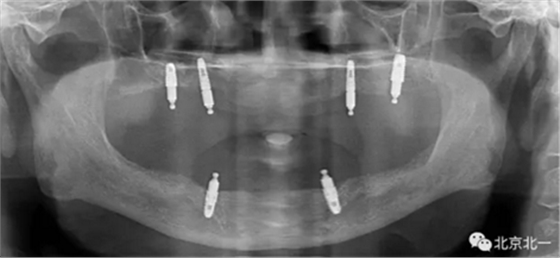

圖一:球帽覆蓋義齒